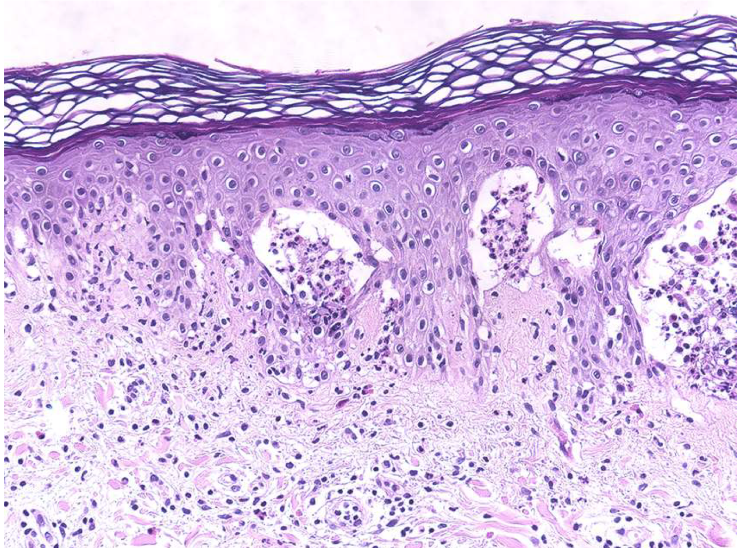

Bandlike infiltrate of lymphocytes @ dermoepidermal junction

Hyperkeratosis, hypergranulosis, sawtoothing (result of chronic basal cell layer injury)

lichen planus